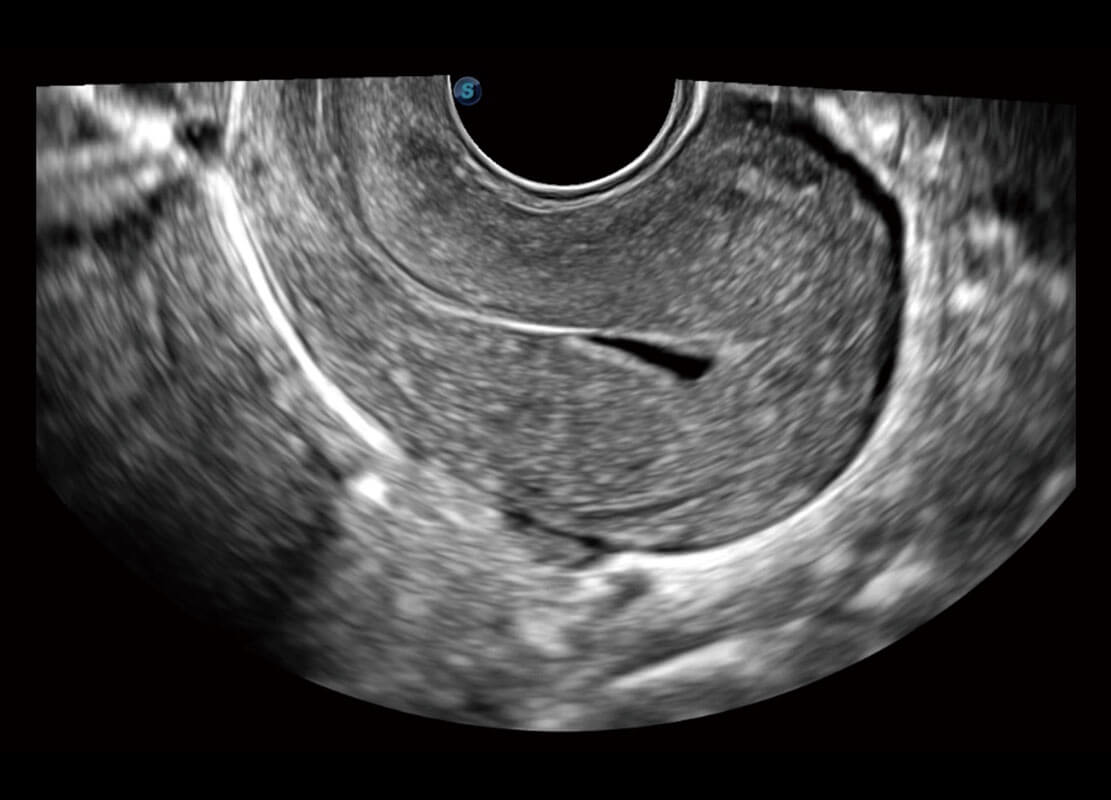

P60优异的图像质量搭载专科探头,在妇科基础疾病的诊断、卵泡生长的监测、输卵管通畅情况的判别等方面为您提供生殖应用方案。

腔内妇科-宫腔分离